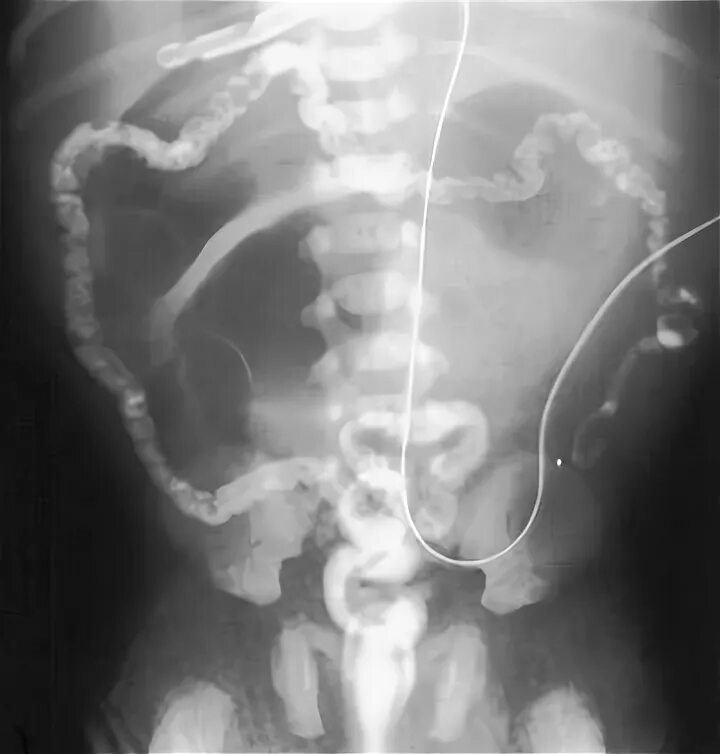

Парез кишечника операция